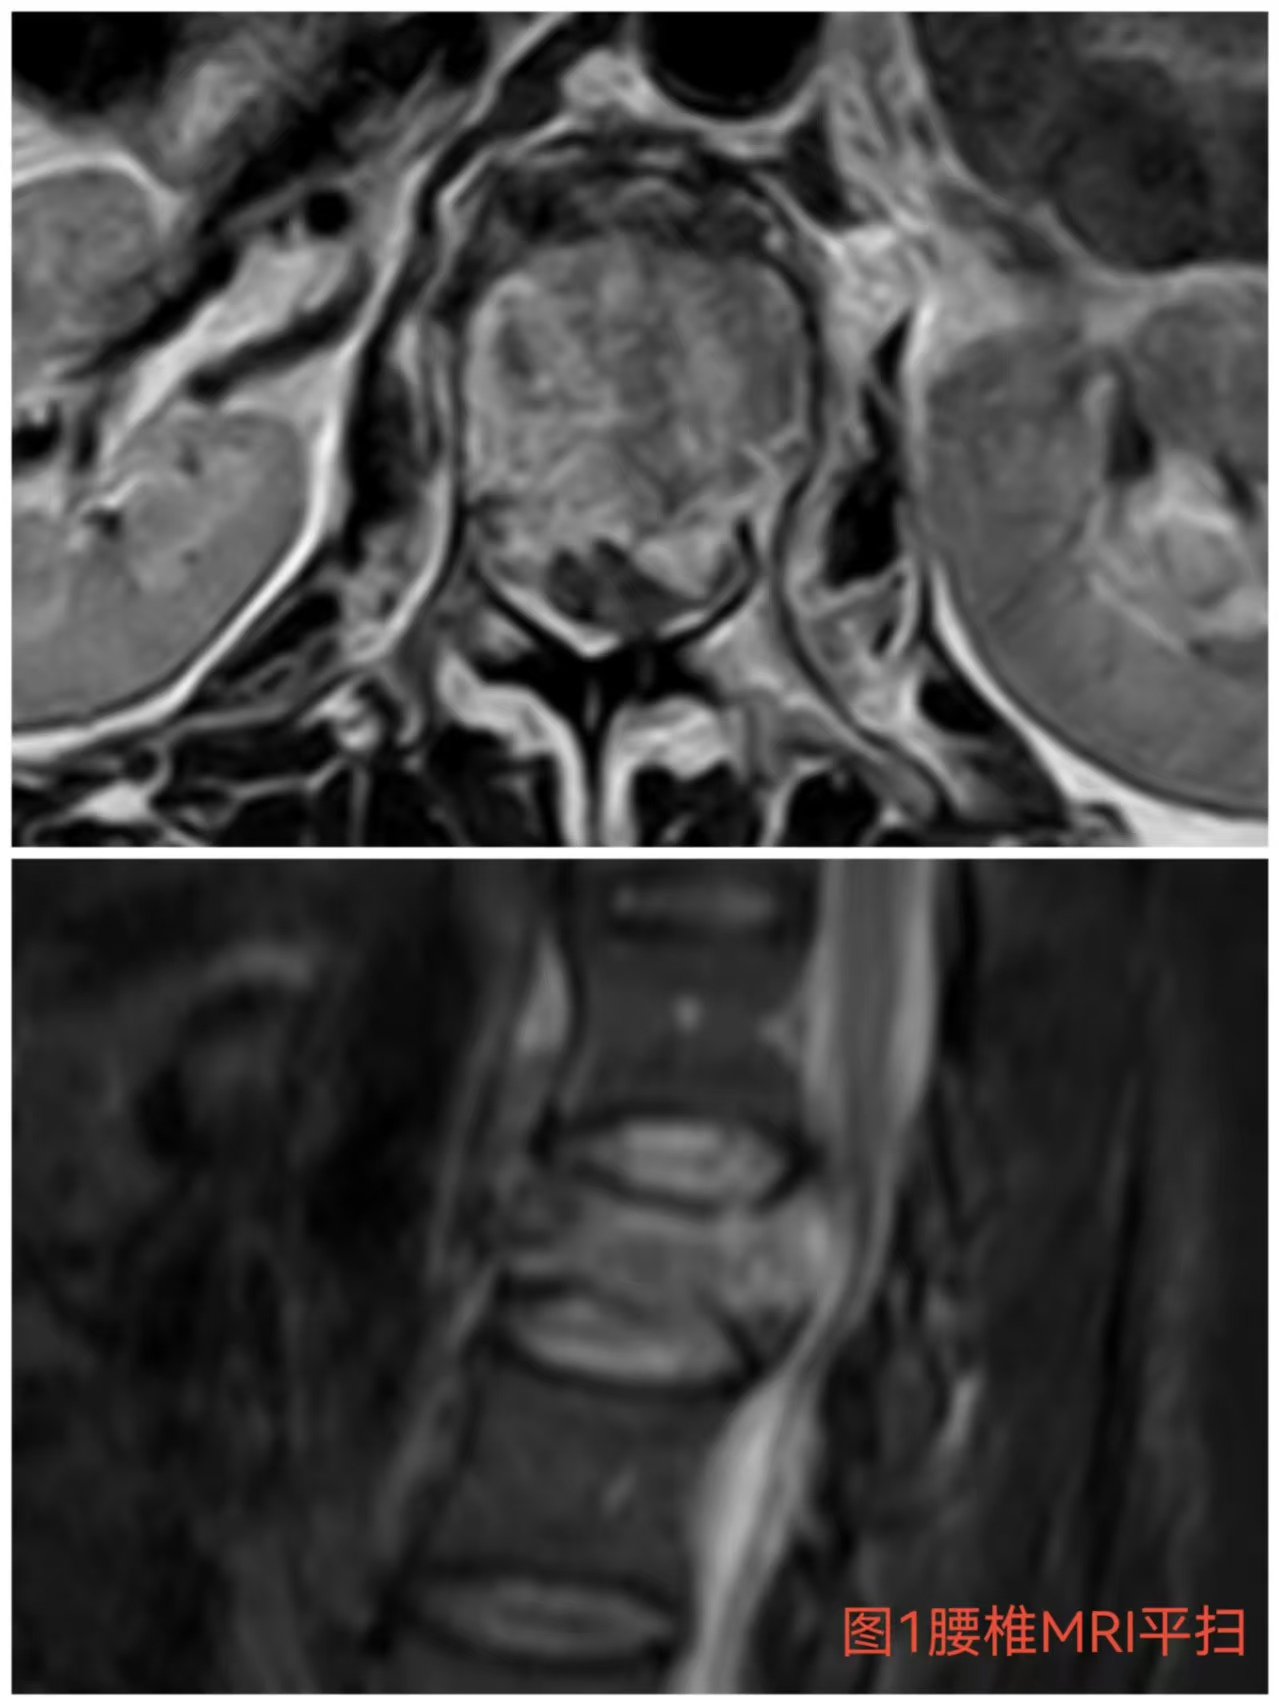

入院时患者躺在床上不可转动,,,,眼神中透漏着深深的无助,,,,关于她来说这种伤情无疑是极重的,,,,尤其是腹股沟以下感受消逝、双下肢肌力0级,,,,这意味着其下肢无法活动及站立,,,,似乎被运气按下了暂停键;;与病人及眷属充分相同病情后,,,,第一时间给予对症治疗,,,,监测患者生命体征,,,,行腰椎核磁检查(图1)提醒:腰1椎体爆裂性骨折,,,,椎体后缘塌陷致骨性椎管狭窄,,,,榨取脊髓神经,,,,连系患者病情及辅助检查可诊断为:“L1椎体爆裂性骨折伴双下肢截瘫”。。。。